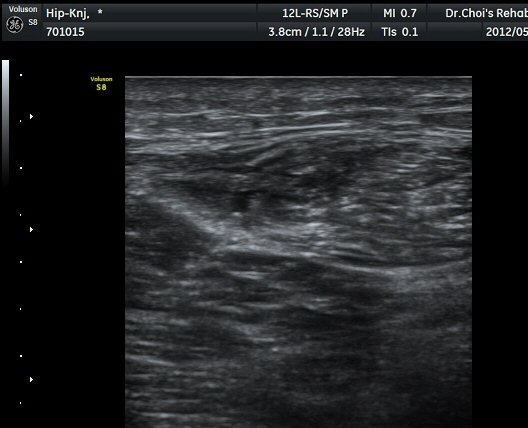

ÀüÇÏÀå°ñ±Ø(AIIS) Ⱦ´Ü¸é °Ë»ç»ó ÀüÇÏÀå°ñ±Ø°ú µÇÅðÁ÷±ÙÀÇ ÈûÁÙÀÌ °üÂûµÈ´Ù(±×¸² 1).

ŽÃËÀÚ¸¦ ¾Æ·¡·Î À̵¿ÇÏ´Ï ´ëÅðÁ÷±Ù³»¿¡ Àú¿¡ÄÚ º¯º¯ÀÌ °üÂûµÈ´Ù(±×¸² 2, 3).

´ëÅðÁ÷±Ù Á¾´Ü¸é°Ë»ç¿¡¼­ ±ÙÀ°³»¿¡ ¼±»óÀÇ Àú¿¡ÄÚ °¢±ØÀÌ °üÂûµÈ´Ù(±×¸² 4, 5).